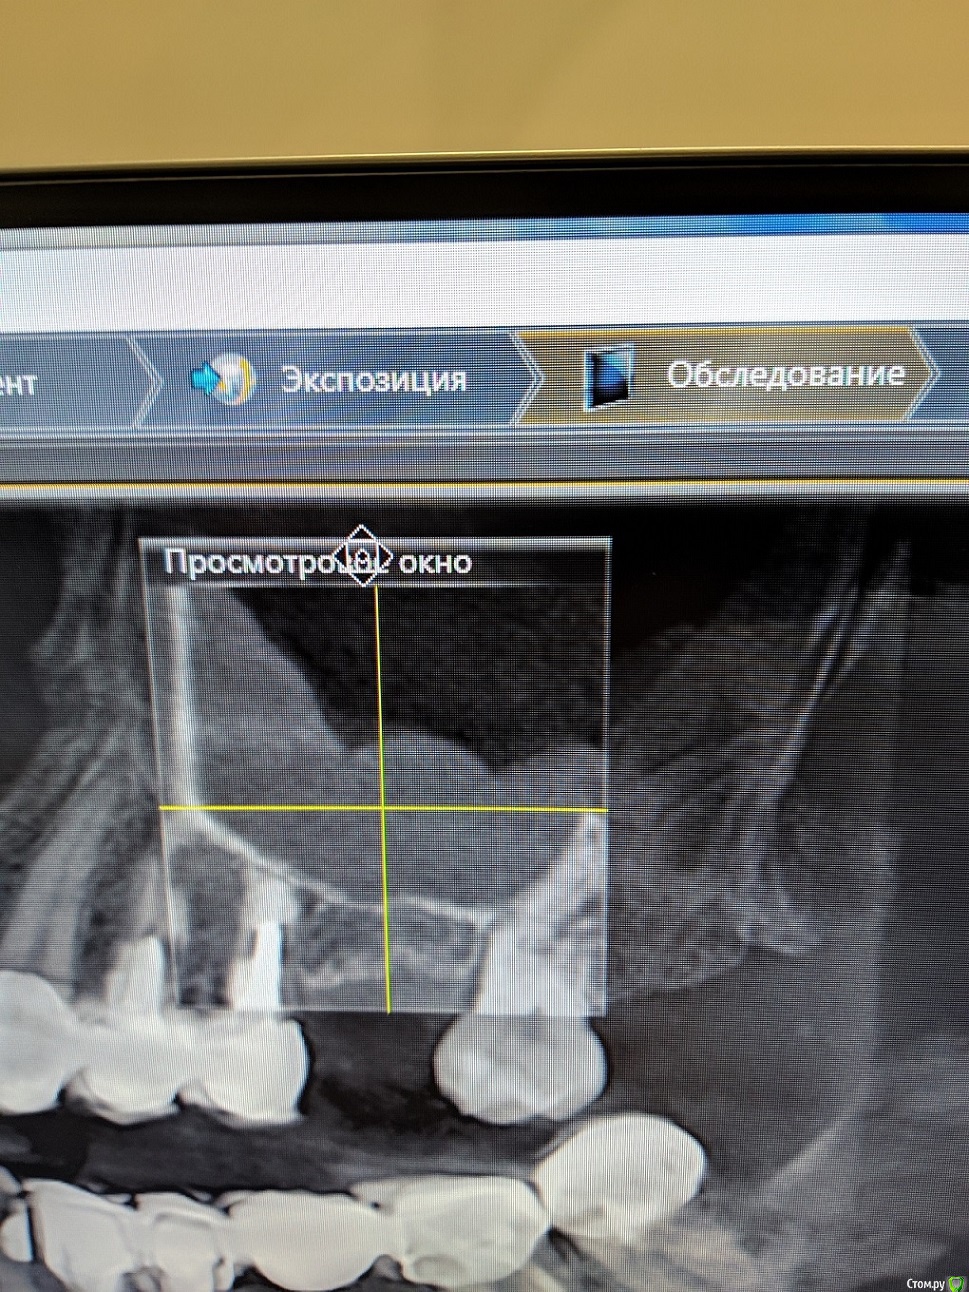

sabik Опубликовано 26 сентября, 2019 Поделиться Опубликовано 26 сентября, 2019 Здравствуйте, подскажите можно ли поставить имплант вместо удаленного 7 мес назад зуба( верхняя 6-ка),приподняв слизистую пазухи на 4мм, в пазухе полипы, не будет ли последствий, или не рисковать и ставить мост? Лор считает, что в пазуху есть необходимость лезть только при открытом синус-лифтинге. Надеюсь срез с КТ правильно сфотографировала. Ссылка на комментарий

red_butler Опубликовано 26 сентября, 2019 Поделиться Опубликовано 26 сентября, 2019 Здравствуйте, подскажите можно ли поставить имплант вместо удаленного 7 мес назад зуба( верхняя 6-ка),приподняв слизистую пазухи на 4мм можно Ссылка на комментарий